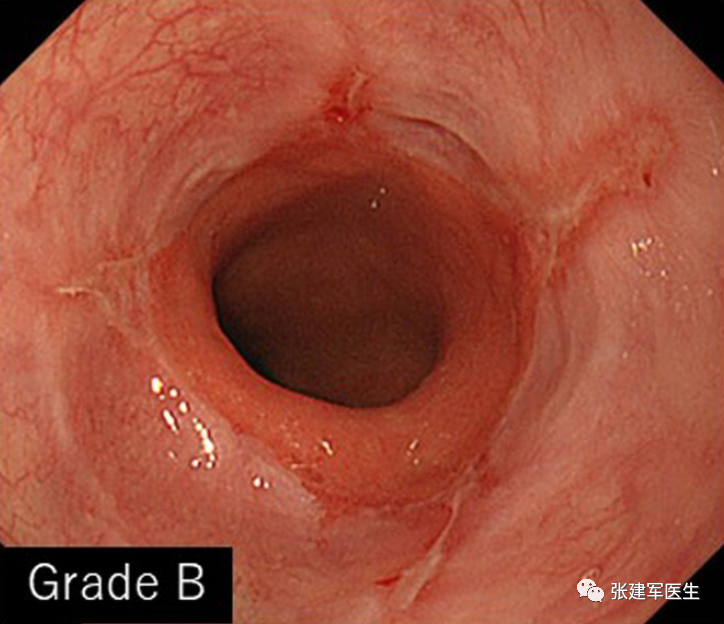

食道炎(Esophagitis),食道中的酸会导致食道内壁发炎。 慢性炎症会导致疼痛、吞咽问题、溃疡甚至出血。

胃十二指肠镜检查

能直观评估食管、胃以及十二指肠粘膜状态,诊断糜烂性食管炎及巴雷特食管(Barrett's esophagus),明确食管裂孔疝的大小及类型,确定食管裂孔疝有无扭转。